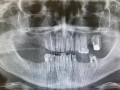

Błędy diagnostyczne oraz techniczne w leczeniu…

Damian Dudek, Maciej Jagielak, Aldona Chloupek, Oliwia Warmusz, Edyta Reichman-Warmusz